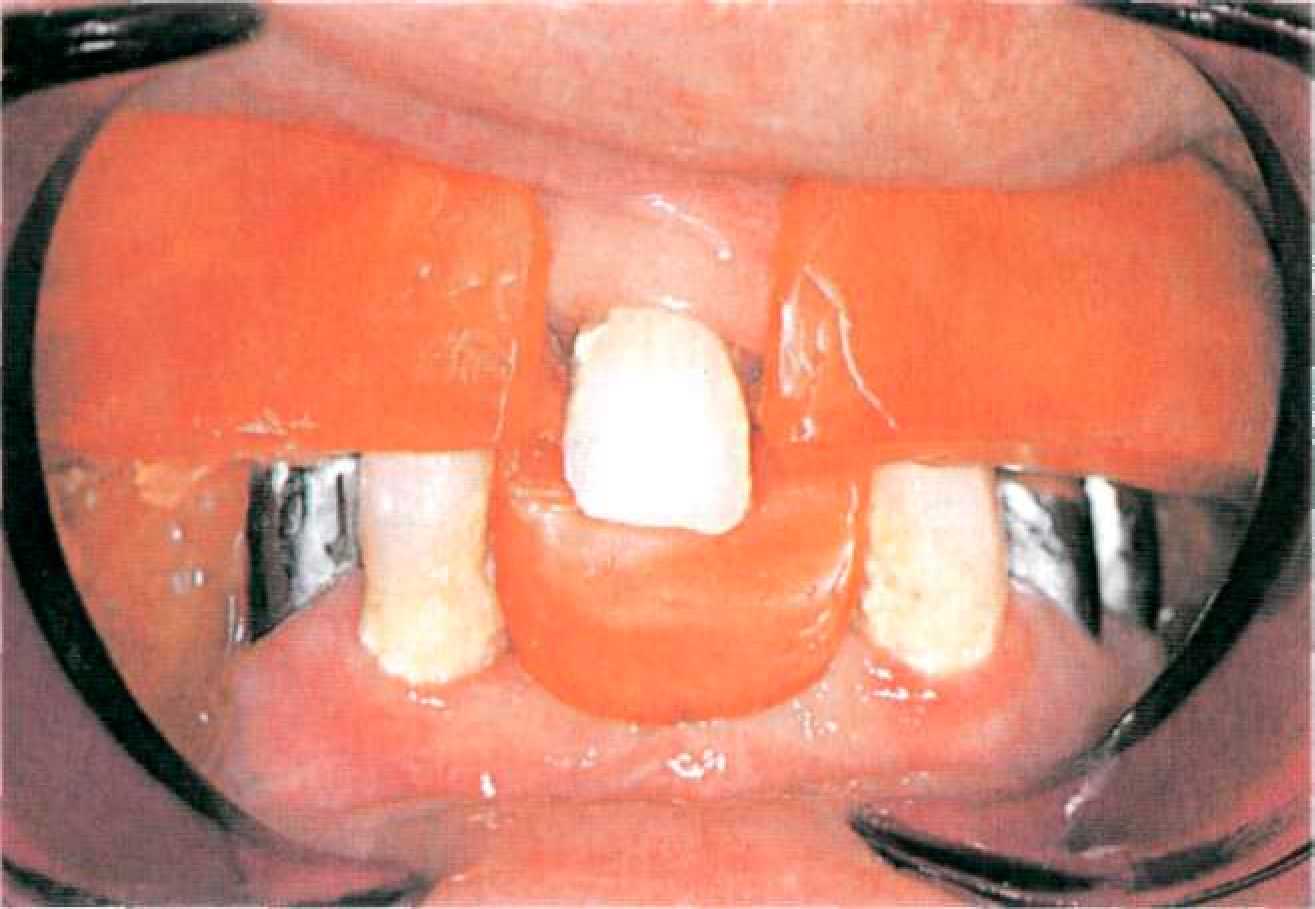

Покрывной протез с телескопическими фиксаторами с фрикционными штифтами Этап 1. После необходимого предварительного обследования, оценки ситуации в полости рта (рис. 127, 128) и санации снимают диагностические оттиски с верхней и нижней челюстей альгинатной массой стандартными ложками, подготавливают диагностические модели из прочного гипса.